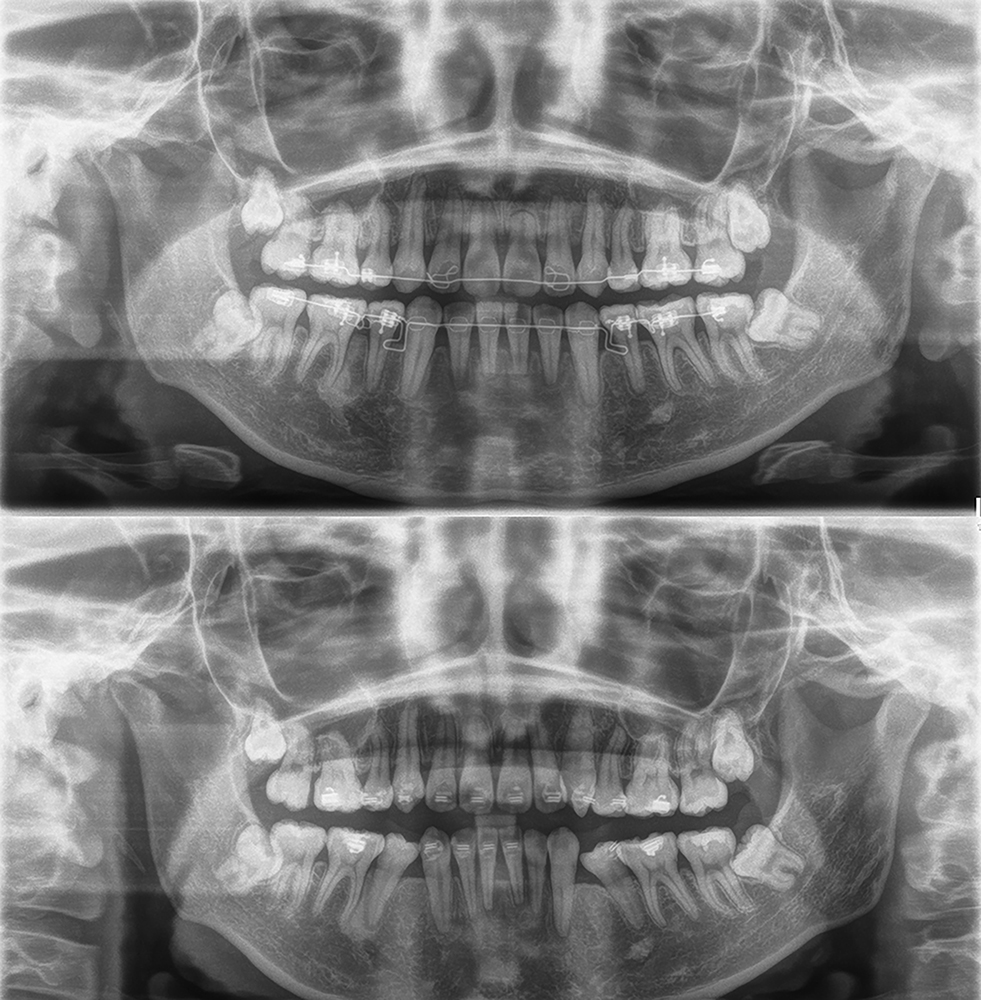

「カマクラデントフェイシャルオーソピディクスオリジナルの取り外しの効くミニマムアクチベータの治療結果」

「子どもの矯正歯科」 「日本歯科専門医機構認定矯正歯科専門医  山本一宏の blog 」 日本歯科専…